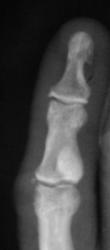

Катенёв Валенти... Дата публикации 19.06.2009, 20:43 Ваше мнение коллеги по поводу локального "уплотнения костной ткани" в средней фаланге 5 пальца левой кисти. Эностоз? Ваше мнение коллеги? Пт, 19/06/2009 - 20:46 #1 Глазков Игорь А... Не на сайте Был на сайте: 11 месяцев 3 недели назад Зарегистрирован: 19.12.2008 - 20:41 Публикации: 1597 что эностоз, но неплохо бы узнать возраст пациента. Прийди к Себе Пт, 19/06/2009 - 20:52 #2 Катенёв Валенти... Не на сайте Был на сайте: 7 лет 3 месяцев назад Зарегистрирован: 22.03.2008 - 22:15 Публикации: 54876 Пациент возраста около 30-ти лет.

Пациент возраста около 30-ти лет.